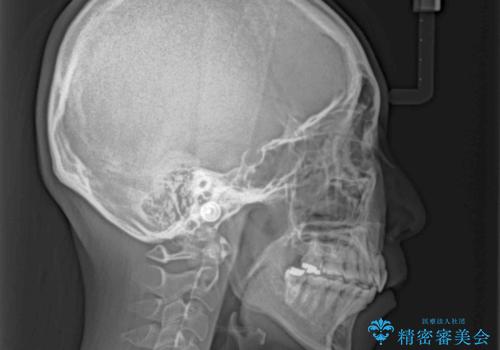

再矯正で突出した口元を引っ込める 抜歯矯正の後戻り

- 抜歯矯正の後戻りで前歯が突出してきていることを気にして来院された患者様です。

口元の突出感を改善するにあたり、抜歯矯正は行うことができないため、奥歯の後方移動とIPR(歯と歯の間を削る)により達成することとしました。

再度後戻りしたときに対応しやすいよう、インビザラインにて矯正治療を行うこととしました。

しっかりと装着時間を守り、ゴムかけにも協力していただいたので、口元を引っ込めることができました。